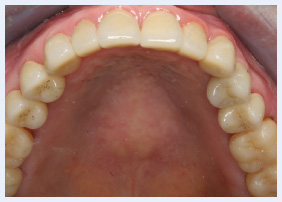

Grinding And Clenching Bruxism Pocket Dentistry Bruxism (brucks is im) is a habit of grinding or clenching your teeth. it can happen in children or adults of any age. people who suffer from bruxism may have one or more of these symptoms: how is bruxism treated? treatment depends on each person’s situation. your dentist may recommend one or more of the following treatments:. People may be oblivious to their bruxism, but family members might notice it. bruxism can abrade and eventually wear down enamel and dentin in the crowns of teeth, damage metal or ceramic dental crowns, and cause teeth to become mobile.

Grinding And Clenching Bruxism Pocket Dentistry Bruxism is a condition where a person grinds, clenches, or gnashes his or her teeth; it can occur when awake or asleep. bruxism that happens while a person is awake is more common, but bruxism that happens during sleep has been studied more. children as well as adults can have this condition. When stressed, your jaw muscles tend to tighten, resulting in teeth grinding and or clenching (also called bruxism). while this can happen without you even realizing it, it can be very dangerous to your teeth. there are lots of techniques you can use to lessen the effects of bruxism. Left untreated, bruxism can cause jaw pain and dental damage. learn more about treatments that can help you stop grinding your teeth. In the context of bruxism, grinding is characterised by dynamic tooth contacts brought about by jaw muscle activities. grinding may or may not be accompanied by sounds. bracing is the equivalent of clenching, but without tooth contact.

Grinding And Clenching Bruxism Pocket Dentistry Left untreated, bruxism can cause jaw pain and dental damage. learn more about treatments that can help you stop grinding your teeth. In the context of bruxism, grinding is characterised by dynamic tooth contacts brought about by jaw muscle activities. grinding may or may not be accompanied by sounds. bracing is the equivalent of clenching, but without tooth contact. Bruxism, characterized by involuntary grinding or clenching of teeth, is a widespread condition with multifaceted implications for oral health, physical well being, and quality of life. Studies show that changes in brain activity like low dopamine, high stress, and poor sleep can all contribute to teeth grinding. dentists can treat the damage caused by bruxism, but understanding the cause is what helps prevent it from coming back. See your dentist or other healthcare professional if you have symptoms that could be caused by grinding or clenching your teeth or if you have other concerns about your teeth or jaws. This series of papers will review the aetiology of bruxism, its impacts and treatment strategies for persistent bruxers who are at risk of, or suffering, tissue damage.